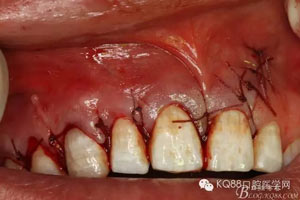

圖11.骨腔填塞膠原蛋白

圖12.縫合創(chuàng)口